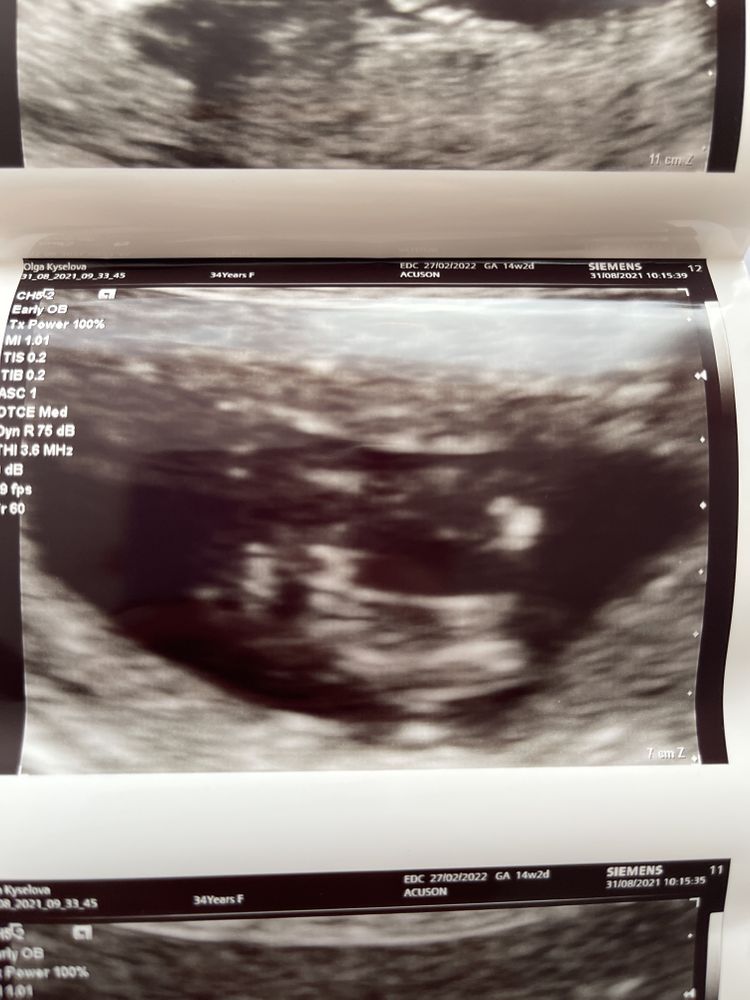

Так вот в ночь перед узи мне приснилось ещё раз … что я пришла на узи определять мальчик или девочка у меня. И узи и акушерка снова мне девчонку показали и сказала.

Узи четко показало …

девочку🥰